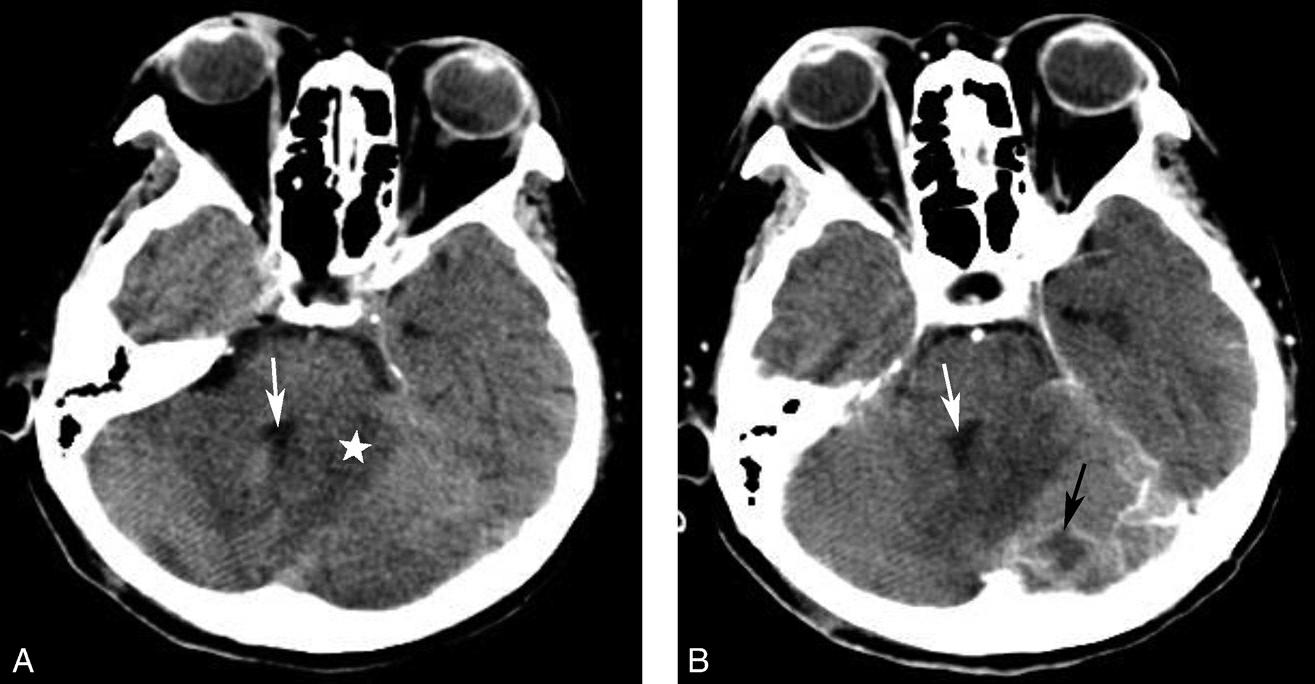

图1-2-4 右侧颈静脉球瘤

A.横断面(骨窗);B.横断面

右侧颈静脉孔区不规则骨质破坏(箭),局部见软组织肿块(☆)